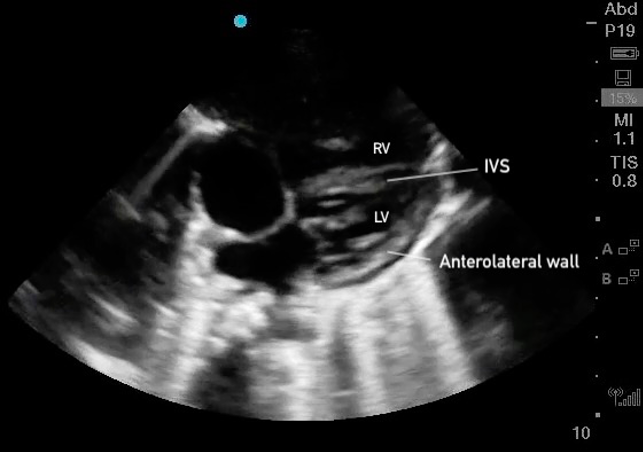

Parasternal Short Axis

The PSAX view provides a cross-sectional image of the LV, allowing simultaneous visualization of multiple walls. It is the preferred view for global assessment of LVfx and RWMAs. This view is useful for assessing wall motion across the anterior, lateral, posterior, inferior, and septal segments, all seen in a single plane at multiple levels (basal, mid, apical) (figure 11).

A circular LV cavity indicates you’re on-axis, while an oval or elliptical shape suggests you’re off-axis and should adjust your probe angle for a true short-axis view.

Figure 11. PSAX at the mid-papillary level with left ventricular walls labeled.

Contractility:

At each PSAX level, all LV walls should contract symmetrically, moving inward toward the center of the circular cavity and thickening evenly during systole. All walls should demonstrate coordinated inward motion and uniform thickening.

Eyeballing Ejection Fraction:

When qualitatively assessing LV function in PSAX, the EF can often be ‘eyeballed.’ From the circular ‘donut’ view at the mid-papillary level, a normal EF should look like the LV cavity volume is shrinking by more than half.